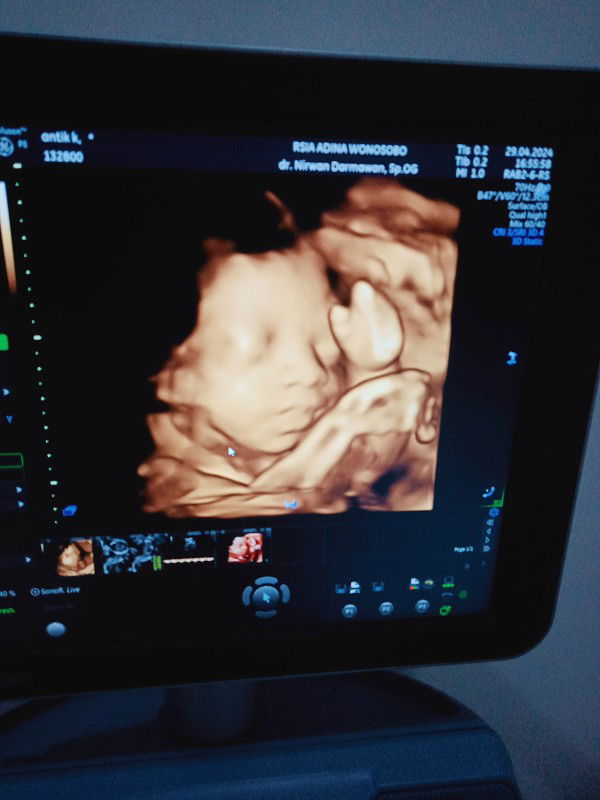

sedang mengandung

Hallo bun...disini ada nggak ya yang HPL 27juli tapi blm ada tanda" mau lounching? Bagi tipsnya donk

HPL 27 juli 2024